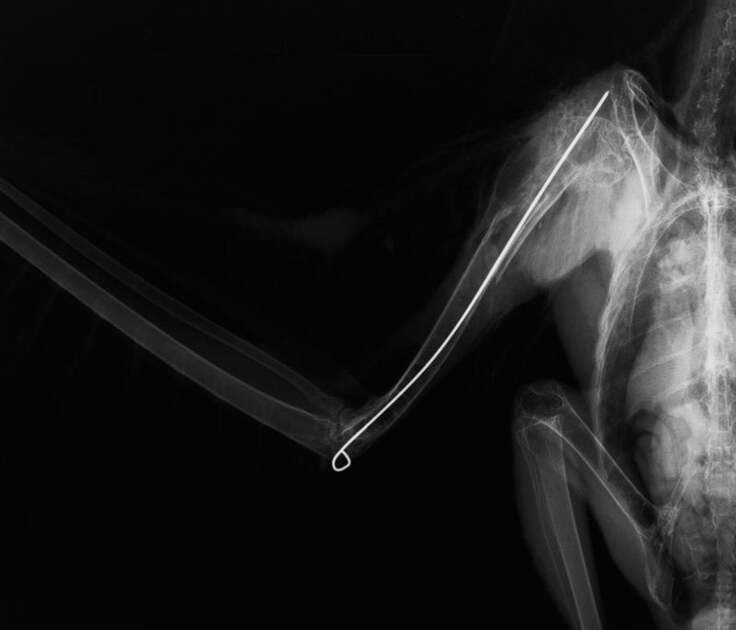

その為、鳥の翼の整復手術でよく用いられる骨と骨をワイヤーピンで固定する手術を行い、内側から骨折箇所を固定することにしました。

幸い、保護されてきたトビは幼鳥とは言え、全長約 50 cmと、ハシブトガラスの成鳥より二回り程大きな体であることと、病院到着時の容体が非常に落ち着いていたことから、麻酔や手術に耐えられると判断し、急遽、その日に手術を行うことになりました。

手術は進み、骨と骨の間に14 cmのワイヤーピンを入れました。

白いのが挿入したピンです。

内部の処置が終わったあと、胸部の圧迫に細心の注意を払いつつ、外からも翼を固定する為にテーピングをしました。

手術は無事終わり、その後、麻酔からの覚醒も良好で、その日の夜にはしっかりと食事も行えていました。